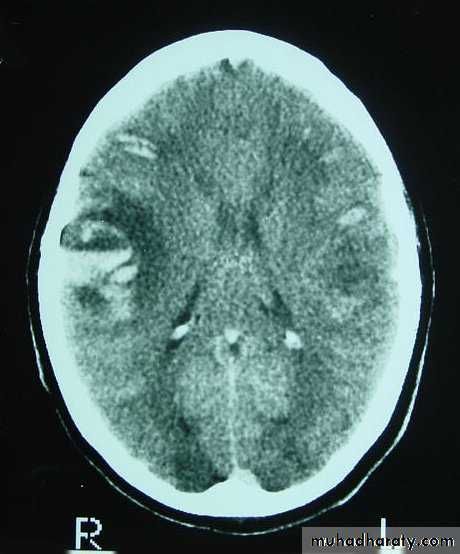

3. Brainstem and hemispheric (Cerebral) Contusion

These are areas of bruising and swellings with intact pia arachnoid, localized or generalized oedema and haemorrhage due to tearing of blood vessels.

3. Cerebral Contusion

Clinical presentations:

1. Prolonged periods of unconsciousness.

2. Focal neurological deficits that persist for longer than 24 hours.

CT scans demonstrates contusions as small areas of haemorrhage in the cerebral parenchyma.

Contusions may resolve with the accompanying deficits or they may persist.